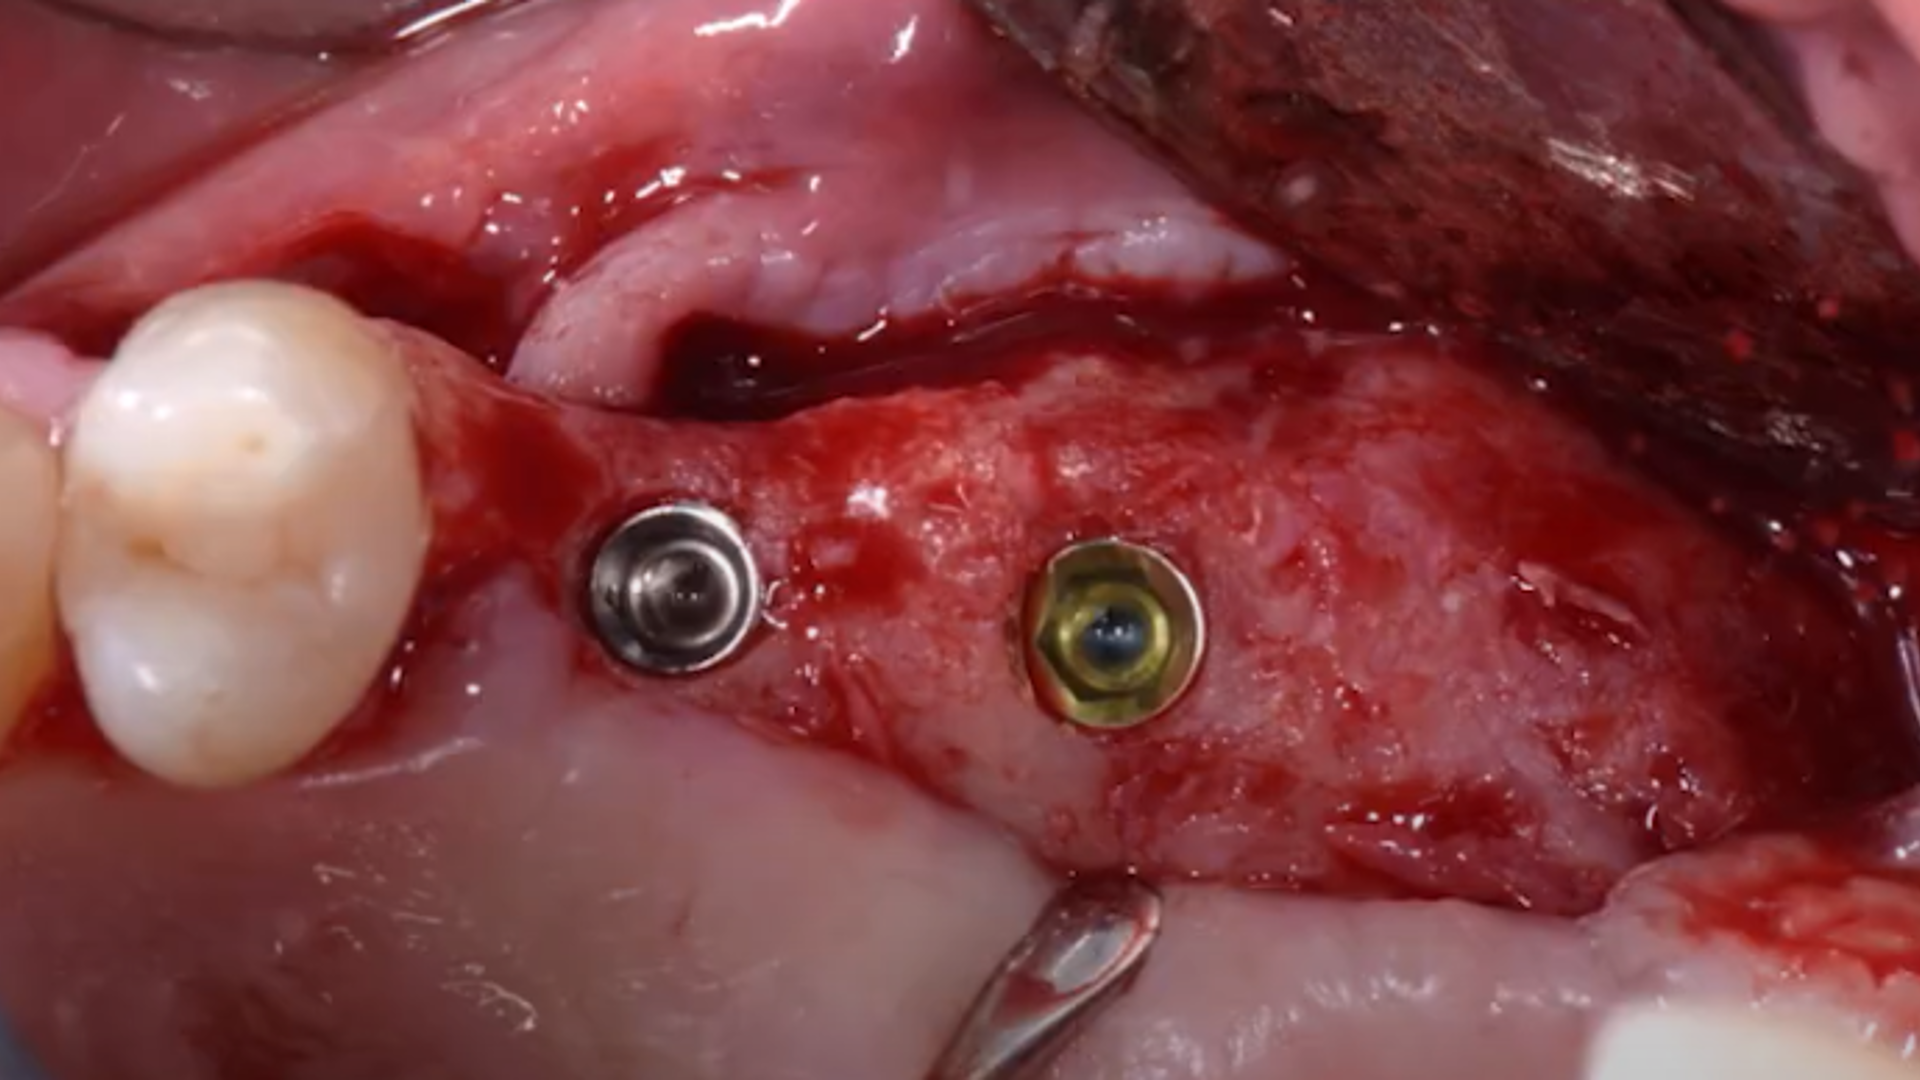

Example of different clinical cases: step-by-step surgical protocol

Osseodensification technique

Clinical video: short implants + Versah crestal sinus lift

Clinical video: Crestal sinus lift and multiple implant placement